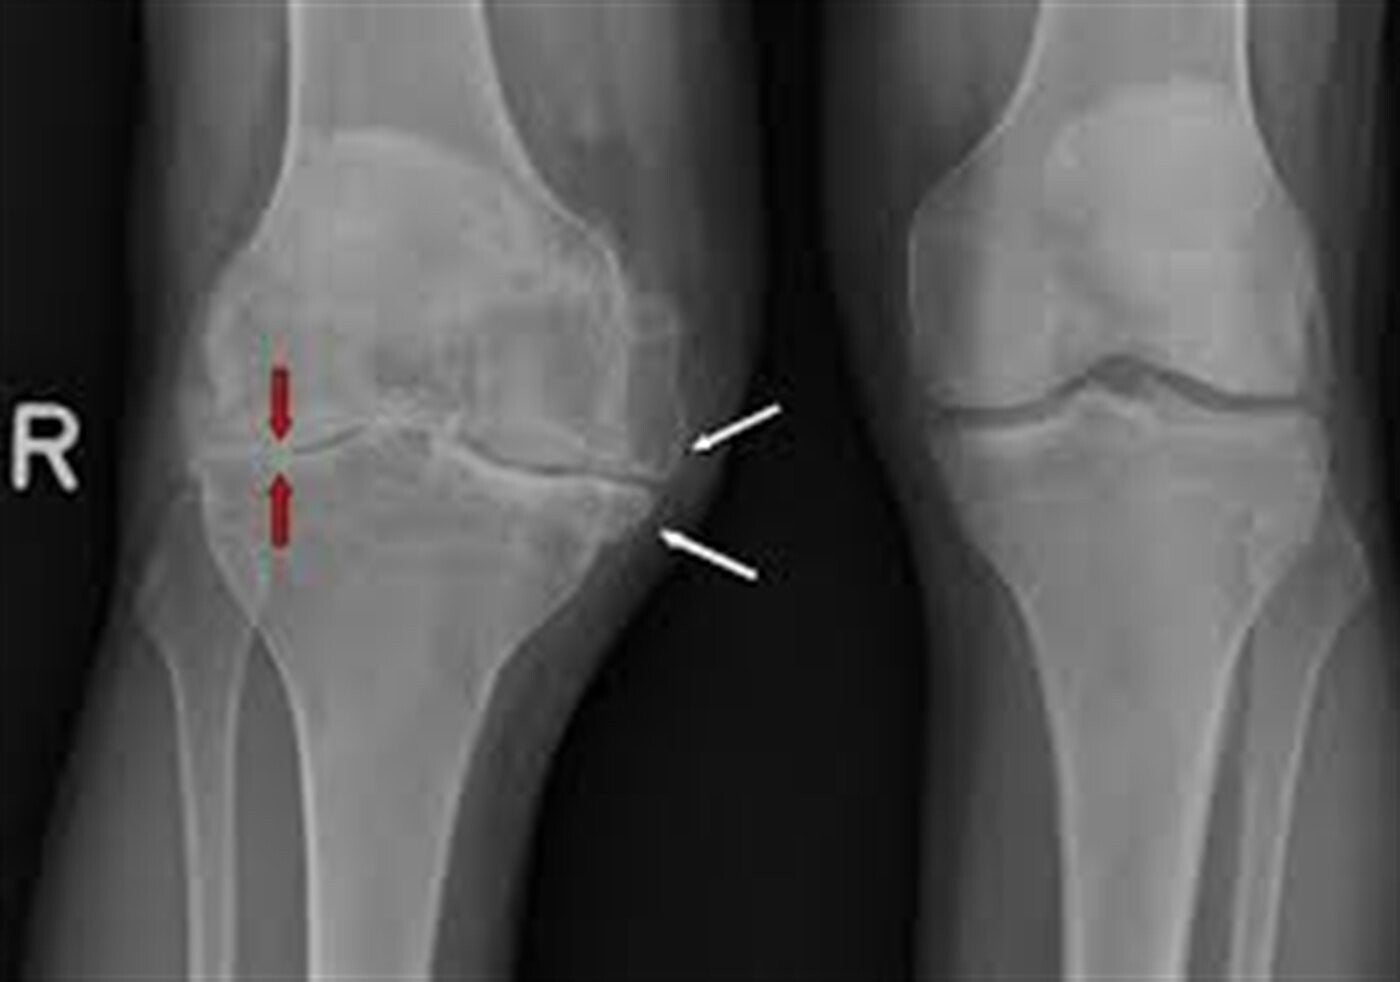

Artrose is de aftakeling van het gewrichtskraakbeen. Tengevolge van slijtage wordt het gewrichtskraakbeen minder elastisch. Er komen scheurtjes in en het wordt dun en onregelmatig. Hierdoor verliest het zijn gladheid, waardoor de knie stijver en gevoeliger wordt.

Niet alleen het kraakbeen ondergaat veranderingen, maar ook het bot. Aan de randen van het gewrichtsoppervlak ontstaan botaangroeiingen, zoals te zien is op de foto. Hierdoor worden de fraaie, gladde oppervlakten in het kniegewricht misvormd.

Er ontstaat een ruw oppervlak met vaak een standafwijking van het onderbeen. (X-of O-beenstand).